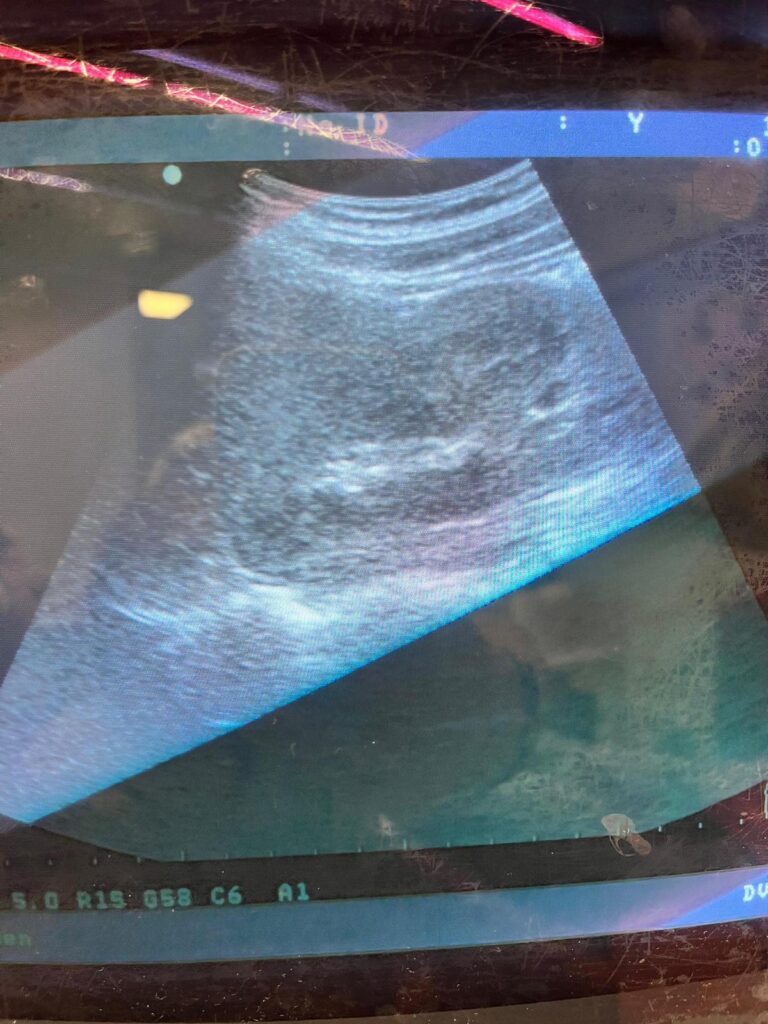

W drugiej części pracowali na aparatach USG, ucząc się podstaw diagnostyki i samodzielnie badając się nawzajem. Zajęcia dały im praktyczny kontakt z nowoczesnym sprzętem i medyczną rzeczywistością.